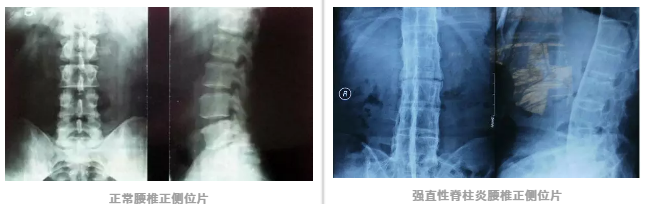

强直性脊柱炎(ankylosing spondylitis,AS)是一种慢性的风湿性炎症。

AS 病变首先累及骶髂关节,然后进一步侵犯脊柱,导致脊柱僵硬、疼痛、活动能力减弱,最终可引起骶髂关节及椎间关节骨性强直。

何升华主任指出,强直性脊柱炎的病理特点是脊柱椎间关节、前后纵韧带骨化,椎间盘钙化,最终导致脊柱强直。

脊柱的弹性及活动度明显减少,椎体抗压抗张能力减弱,加之强直性脊柱炎还常伴有严重的椎体骨质疏松,脊柱严重后突畸形,使强直性脊柱炎病人发生脊柱骨折的几率明显高于正常人。